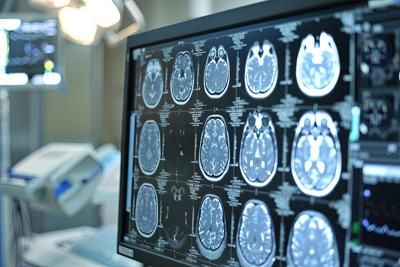

Il documento affronta in maniera organica tutti gli aspetti fondamentali per la corretta implementazione delle nuove terapie anti-Alzheimer e definisce innanzitutto i criteri per la selezione dei pazienti, individuando come candidati ideali coloro che presentano decadimento cognitivo o demenza di grado lieve, dovuta alla malattia di Alzheimer. E’ importante sottolineare – avvertono i neurologi – che queste terapie non sono indicate per tutti i pazienti, né per tutti gli stadi della malattia. Ampio spazio è dedicato alla diagnosi precoce e appropriata, con l’obiettivo di stabilire criteri chiari per l’individuazione dei pazienti nelle fasi iniziali e di semplificare il percorso diagnostico, evitando esami invasivi o costosi quando non necessari.

L’Epa promuove inoltre l’impiego dei biomarcatori plasmatici come valida alternativa ai marcatori liquorali e alle indagini Pet, così da garantire una maggiore accessibilità diagnostica in tutte le regioni italiane. In collaborazione con Sibioc – Società italiana di biochimica clinica e biologia molecolare clinica, sono in corso la validazione dei parametri biochimici, la definizione dei cut-off e la standardizzazione dei protocolli. E’ stato fondamentale – riferisce la Sin – anche il contributo della radiologia e della medicina nucleare, con cui il documento definisce quali tipologie di risonanza magnetica e di indagine Pet utilizzare per identificare i pazienti più idonei e ridurre il rischio di effetti collaterali. Con la Società italiana di geriatria, Epa lavora alla definizione dei criteri clinici per riconoscere le persone fragili, pre-fragili o complesse, che potrebbero non essere candidati ideali per questi trattamenti. Particolare attenzione è rivolta all’equità di accesso e al rafforzamento della rete dei Centri per i disturbi cognitivi e le demenze (Cdcd), che avranno un ruolo centrale nella selezione e nel monitoraggio dei pazienti, assicurando uniformità di trattamento su tutto il territorio nazionale.